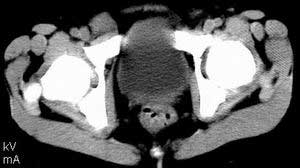

| 患者,男,9岁,因右下腹包块入院,血象不高,不规则发热,常超40度。 平扫: ![]() ![]() ![]() ![]() ![]() ![]() ![]() ![]() ![]() ![]() ![]() ![]() ![]() ![]() ![]() ![]() ![]() ![]() 增强: ![]() ![]() ![]() ![]() ![]() ![]() ![]() ![]() ![]() ![]() ![]() ![]() ![]() ![]() jiajie发言:骶椎右前区不规则软组织肿块,边缘光整,密度均匀,增强后均匀强化,右腹股沟区可见肿大淋巴结,临床有时发热,考虑淋巴瘤,儿童盆腔肿瘤应与神经母细胞瘤和横纹肌肉瘤鉴别。 longzhanghui发言:印象:盆腔右后壁不规则软组织肿块,并向前延伸.似为多个肿块融合,呈中等强化.初步考虑淋巴瘤. 听蝉观竹发言:右侧髂内、外组淋巴结肿大,从其形态和融合的情况看,同意大家意见-----考虑恶性病变,但是9岁男孩还要注意检查睾丸情况,有无隐睾? 常常类似情况是隐睾发生精原细胞瘤淋巴结转移,这个病例也要注意这一点!!! 广东凌发言:大家好,在这里我想说一下个人观点,我建议上传图片的同志能否辛苦一点就是把病史和图片都上传完整一点,比如这个病人的腹膜窗,并且这个病人的肠道的准备也是不怎么好,就从现有的质料看:病灶属于淋巴结肿大当无大的争议,有融合趋势,其内无坏死,边缘强化为主,故考虑:淋巴瘤!建议用腹膜窗看一下和肠道的关系! 阿圣发言:病灶属于淋巴结肿大当无大的争议,有融合趋势,其内无坏死,边缘强化为主,故考虑:淋巴瘤 结果是:淋巴瘤 病例来源:ct762。由宁静致远发布: http://www.radinet.com.cn/forum_view.asp?forum_id=4&view_id=2182 |